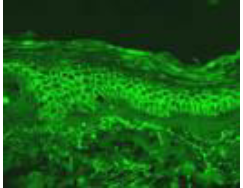

Describe the immunoflourescence of PV

Intracellular (netlike-between keratinocytes) IgG and C3